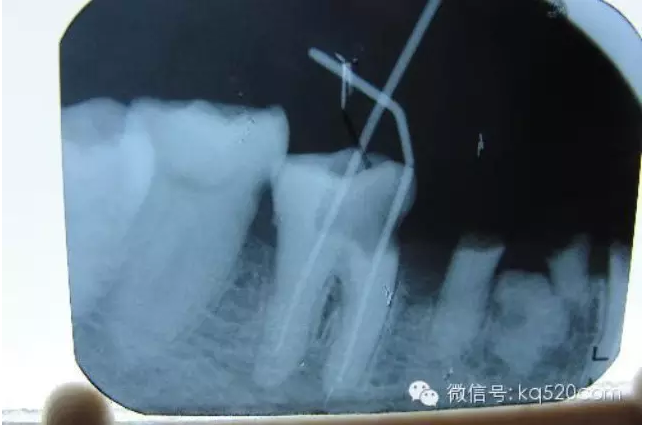

前面我們講過,牙齒內(nèi)部實(shí)際上是一個(gè)空腔,這個(gè)空腔我們稱之為“根管系統(tǒng)”。同單純的“爛神經(jīng)”相比,“根管治療”不僅僅是要將“根管”中的牙髓“殺死”,還要將牙髓從“根管”中清除出來,然后要進(jìn)行徹底清理和嚴(yán)格消毒,并用人工的充填材料將“根管”嚴(yán)密填塞。這就是所謂的“根管治療”。一個(gè)“根管治療”做得是否完善,會(huì)在很大程度上決定了這顆牙齒的壽命。而且,不僅僅是對(duì)于牙髓炎,牙齒的其他疾?。ㄈ绺庵苎椎龋┮残枰捎酶苤委煹姆椒ú拍艿玫街斡膫鹘y(tǒng)的根管治療三部曲(即根管預(yù)備、根管消毒和根管充填)來講,一般的根管治療需要三次。但是這僅僅是理論上的情況,實(shí)際上因患者而異,因牙而異,因醫(yī)生的技術(shù)水平而異?,F(xiàn)代根管治療技術(shù)有了飛躍性的發(fā)展,有些根管治療甚至可以一次完成。